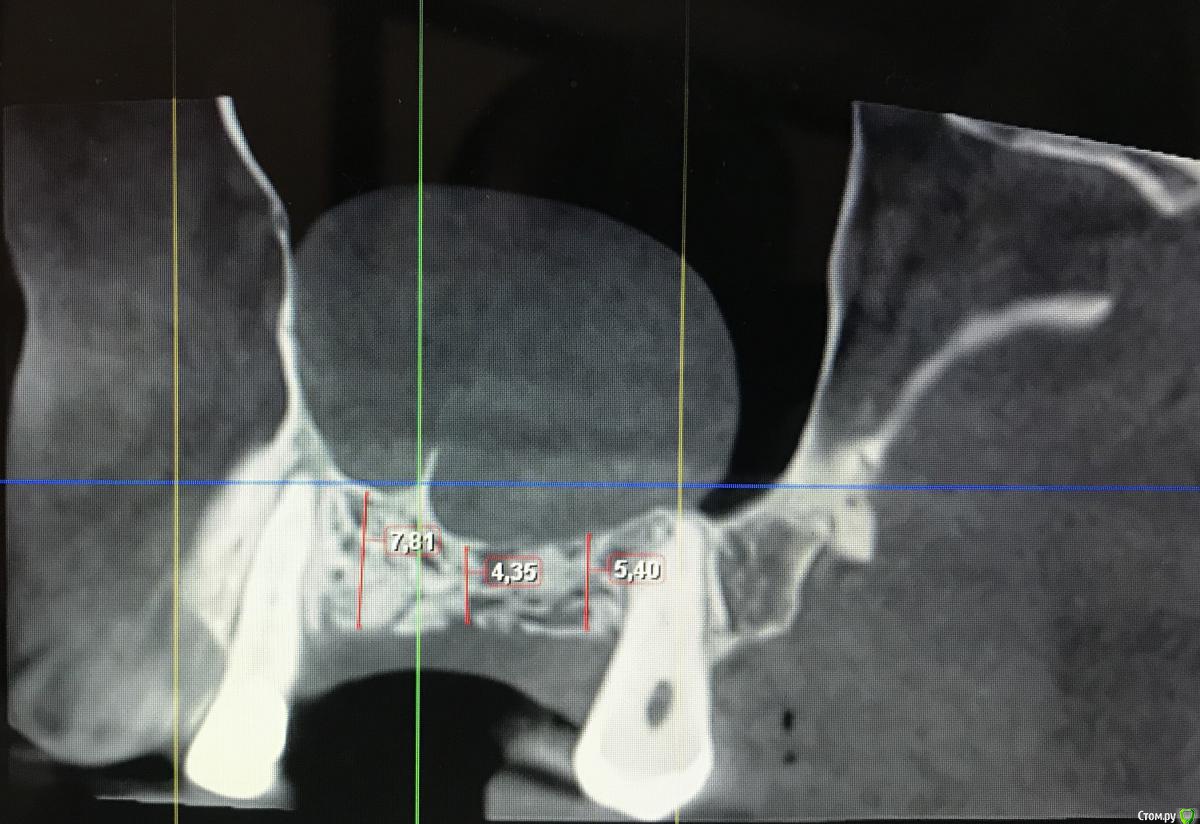

Дмитрий Л. Опубликовано 4 августа, 2020 Поделиться Опубликовано 4 августа, 2020 Неплохое кт, это планмека? Либо 4 мм имплант тишью левел, не затрагивая гайморову, либо открытый синус с croco eye. Ссылка на комментарий

Kilgen Опубликовано 24 августа, 2020 Поделиться Опубликовано 24 августа, 2020 Закрытый с.л + т.л 6 мм Ссылка на комментарий

Александр07 Опубликовано 30 августа, 2020 Поделиться Опубликовано 30 августа, 2020 Неплохое кт, это планмека? Либо 4 мм имплант тишью левел, не затрагивая гайморову, либо открытый синус с croco eye.Если мануал высокий и уверенность и опыт есть в закрытии перфорации то пошёл бы по ядаху но там высокий риск образования большой перфы, поэтому хорошая альтернатива это короткие широкие импл и закрытый с л Ссылка на комментарий

Snow Doc Опубликовано 1 сентября, 2020 Поделиться Опубликовано 1 сентября, 2020 Плюсую к 6мм Тл. Ещё и септа неприятная, по всей видимости, для открытого. Ссылка на комментарий